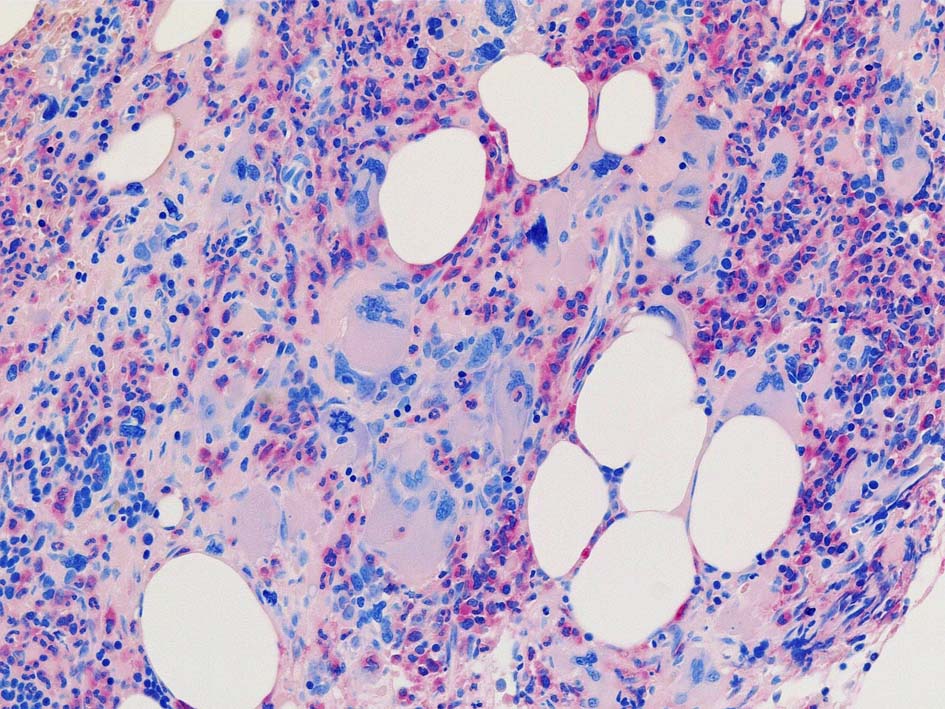

77year-old female. 40歳時polycythemia veraと診断されていた.

[注] この症例は詳細は不明であるが, 過去にPVと診断されているため, PVに伴う二次性のmyelofibrosisの診断になる.

黒染する弾性線維の増生のほか, 赤く染まる膠原線維の増生が確認される. MF-2 fibrosis. 鍍銀染色の核染色をすると膠原線維の赤染がわからなくなるので行わない.